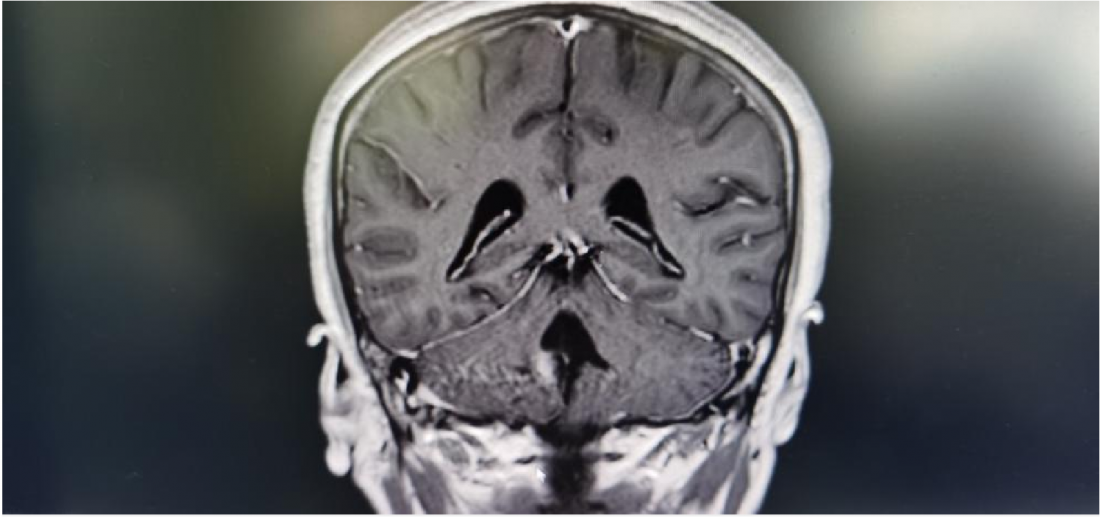

MR显示桥脑右侧高信号影,肿瘤位于四脑室界沟上方之桥脑部分,邻近面丘及动眼神经核,因此患者出现面瘫。

肿瘤位于桥脑与延髓交界处

面神经丘受压明显

术后MR: